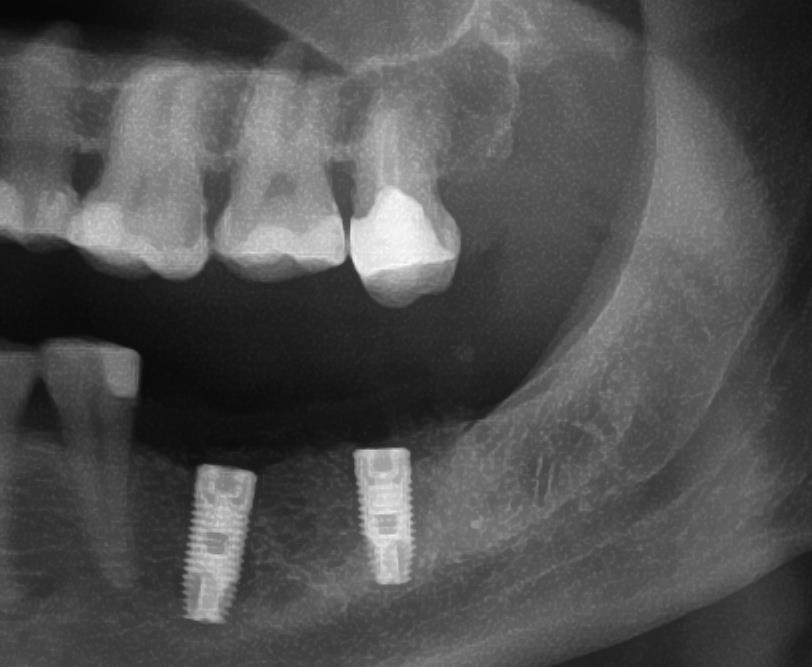

Имплантация Q-имплантами Trinon

Система зубных имплантов Q-Implant была специально создана для широкого применения в области дентальной имплантологии. При разработке этой системы усилия были сфокусированы на том, чтобы сделать ее простой в использовании и лишить многих недостатков, присущих другим системам имплантации. Одноэтапный эндооссальный Q- имплант изготовлен из титана и не содержит компонентов, усложняющих проведение дальнейшего ортопедического лечения. Благодаря самонарезающей резьбе имплантата достигается отличная первичная фиксация и устойчивость, что дает возможность немедленно установить временную коронку. Трансгингивальное заживление снимает необходимость в проведении последующего хирургического вмешательства, а внутрикостная поверхность имплантата, подвергнутая пескоструйной обработке, позволяет сократить период остеоинтеграции. Вышеперечисленные преимущества, а также зеркальная отделка поверхности головки имплантата, способствуют быстрому заживлению и

Q-импланты обладают резьбой с самонарезающим шагом, что способствует «бережной» работе с костной тканью и атравматическому внедрению имплантатов с минимальным усилием. Даже при работе с губчатой костной тканью верхней челюсти обеспечивается прекрасная первичная стабильность. Максимальное внимание уделялось разработке прогрессивной спиральной резьбы с продольными сечениями, полученными путем фрезерования, которая обеспечивает уменьшение нагрузки и равномерное распределение давления по всей площади кости челюсти. Продольные сечения также служат для ограничения вращения имплантата. Костная стружка, собирающаяся вокруг имплантата в процессе установки, является дополнительной поддержкой в процессе остеогенеза.